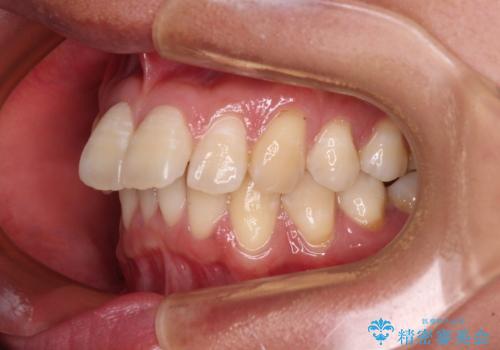

- 上顎前歯の突出感を気にして来院された患者様です。

舌の突出癖の影響で、歯列が前方に飛び出いた形態となっている状態でした。

抜歯矯正とするような歯列ではないため、舌のトレーニングを行いながら歯列を側方に拡大させることで口元の突出感を改善することとしました。

横顔は元々突出した印象ではなかったのですが、上顎前歯の角度が改善したことで、唇の閉じにくさが改善されました。